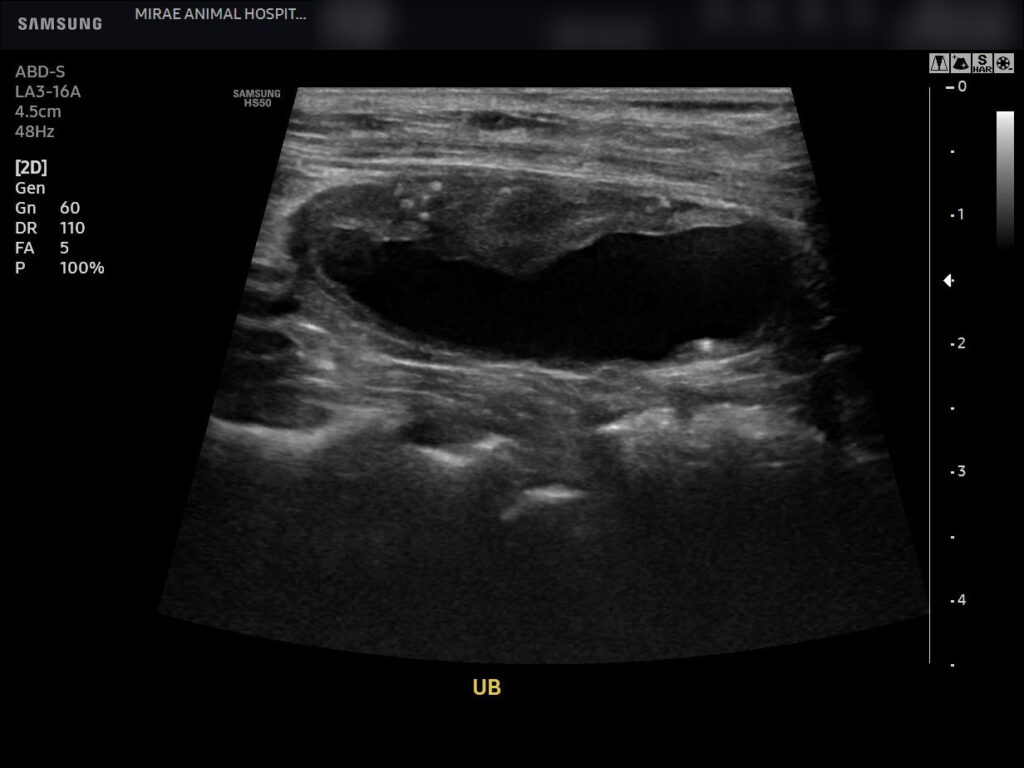

복부 초음파 검사

초음파 검사에서도 방광 내 결석들이 명확히 관찰되었으며, 방광 벽의 구조를 함께 평가한 결과 결석으로 인한 자극 소견은 있었으나 천공이나 심각한 염증 소견은 확인되지 않았습니다.

환자의 복부 초음파 사진 / 출처: 미래동물의료센터

수술 한 달 후 재진 시 복부 초음파 검사를 통해 방광 상태를 다시 확인했습니다.

수술 한달 후 초음파 / 출처: 미래동물의료센터

초음파 검사 결과 방광 내 결석은 재확인되지 않았으며, 방광 구조 역시 안정적인 상태로 유지되고 있었습니다. 재진 시 진료에서 방광결석은 재발 가능성이 있는 질환이기 때문에 방광 자극을 최소화하고 결석 재발 위험을 낮추기 위해 결석 처방 사료 급여를 권장드렸으며, 정기적인 방광과 소변 상태 확인 및 추적 검사의 중요성에 대해 안내드렸습니다.